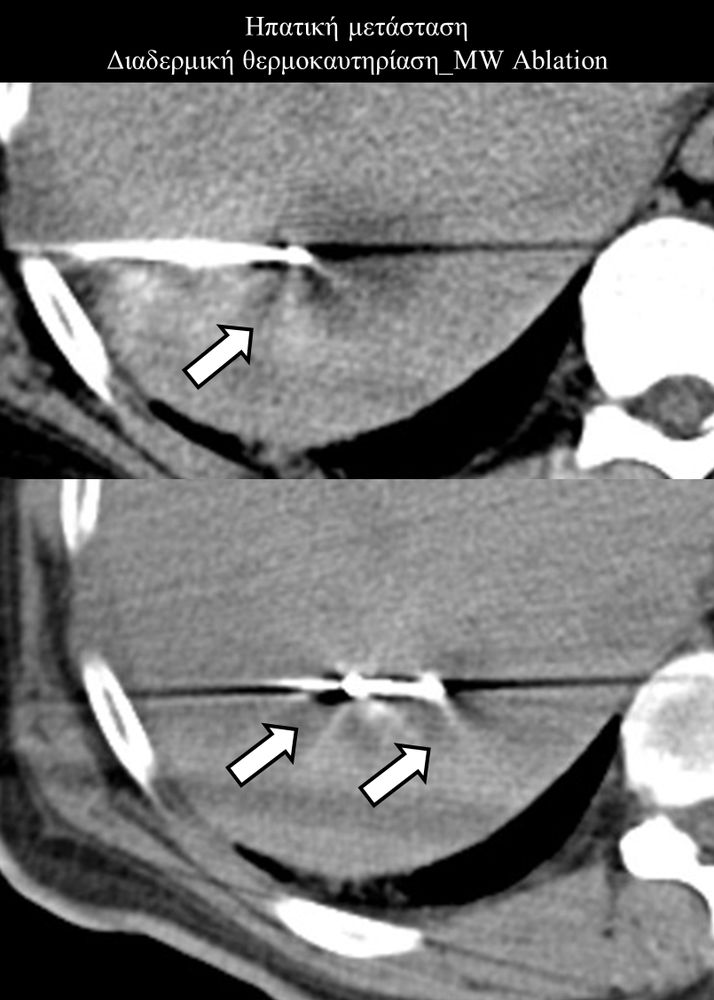

Πρόκειται για την πιο σύγχρονη τοπική θεραπεία όγκων του ήπατος, του νεφρού, του πνεύμονα, των οστών και των όγκων μαλακών μορίων. Παθοφυσιολογικά βασίζεται στην τοπική καταστροφή των καρκινικών κυττάρων με τη δημιουργία ιδιαίτερα υψηλών θερμοκρασιών εντός του όγκου. Αυτό επιτυγχάνεται με τοποθέτηση ειδικών ηλεκτροδίων εντός του όγκου υπό ακτινολογική καθοδήγηση (αξονικός τομογράφος ή υπέρηχος). Τα ηλεκτρόδια αυτά παράγουν υψηλή θερμοκρασία είτε με τη βοήθεια ραδιοσυχνοτήτων (RFablation), είτε με τη βοήθεια μικροκυμάτων (MWablation) και προκαλούν πηκτική νέκρωση των καρκινικών κυττάρων χωρίς να επηρεάζουν τα φυσιολογικά κύτταρα.Το αποτέλεσμα είναι μόνιμο.